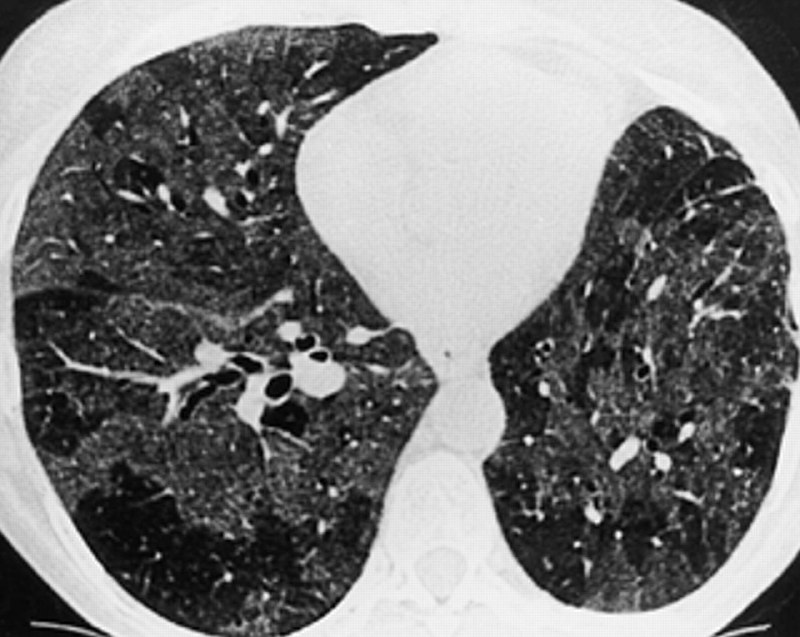

🫁 Российские врачи научились диагностировать «попкорновую болезнь» лёгких по нарастающей одышке и нарушению сна

Также признаками облитерирующего бронхиолита могут быть сухой кашель, свистящее дыхание, быстрая утомляемость, учащенное сердцебиение. В тяжёлых случаях — цианоз при развитии дыхательной недостаточности.